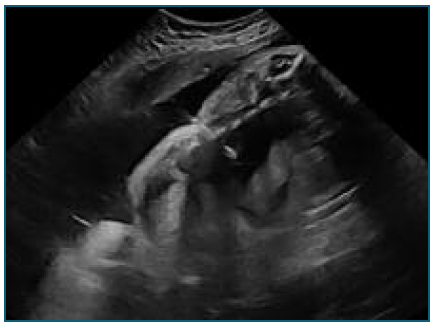

The shunt placement, at 32 weeks and 3 days (Figure 2), occurred without complications, although laborious due to fetal positioning, pleural fluid was collected for analysis. The shunt appeared to be functioning with clear improvement in effusion (Figure 3).